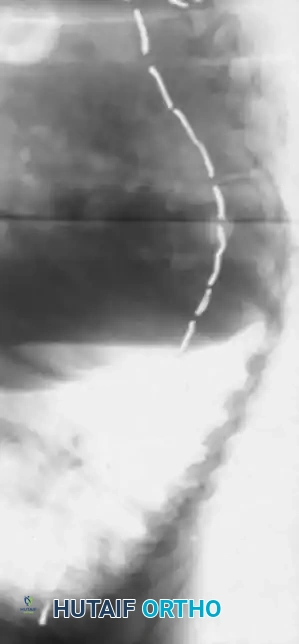

* Including the Pelvis: Mandatory for nonambulators with fixed spinopelvic obliquity. If bending or traction films reveal more than 10 to 15 degrees of L4 or L5 tilt relative to the interiliac crest line, the fusion must extend to the pelvis.

Image

Maintaining physiological lumbar lordosis is paramount in insensate patients fused to the pelvis. Proper sagittal alignment distributes body weight equally beneath the ischial tuberosities and posterior thighs, drastically reducing the risk of pressure sores over the coccyx and sacrum.